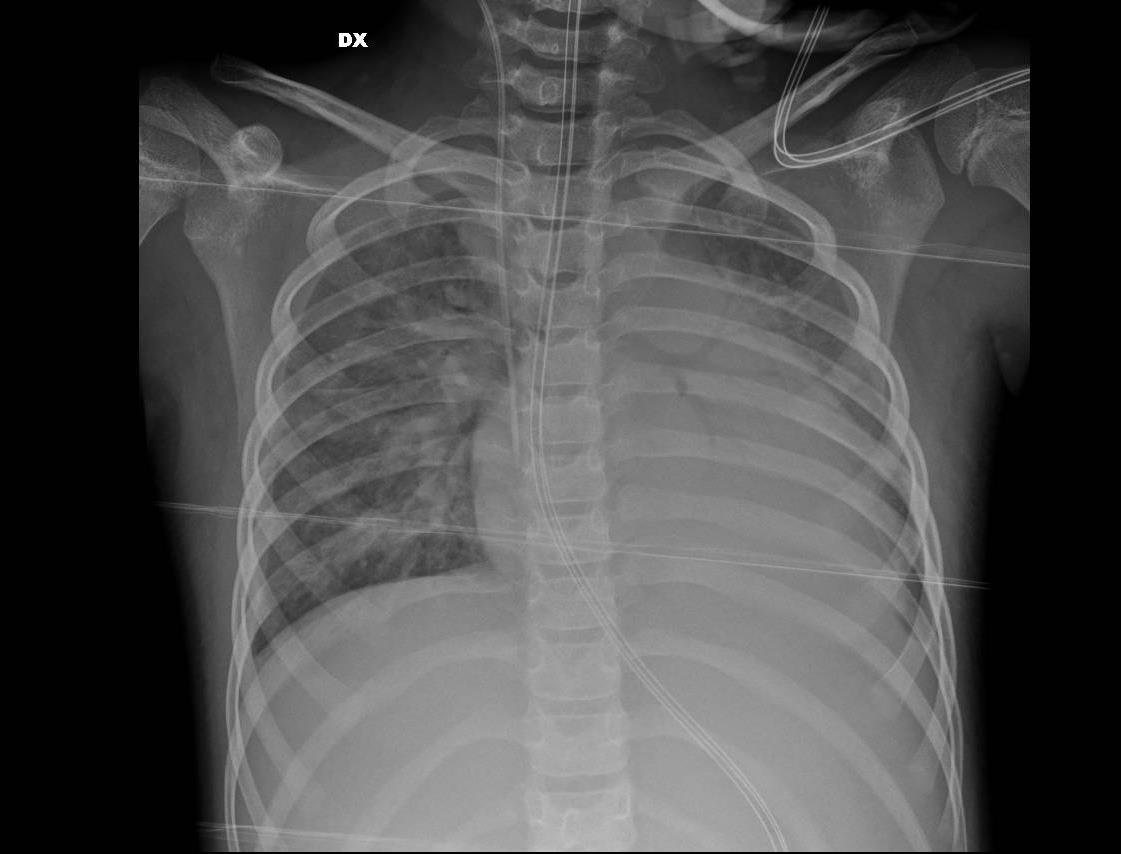

Pediatric COVID-19: MIS-C

Thoracic abnormalities

Cardiovascular abnormalities

Cardiomegaly

CHF or cardiogenic edema

Pulmonary parenchymal abnormalities

Lower lobe atelectasis

Bilateral opacities( ARDS)

Consolidation

Pleural abnormalities

Small pleural effusion

Mediastinal and hilar lymphadenopathy